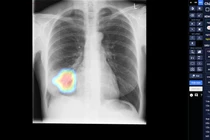

Ra mắt tháng 6/2020, DrAid là sản phẩm AI trợ lý bác sĩ cho chẩn đoán hình ảnh y tế hoàn chỉnh đầu tiên của y tế Việt Nam. Sản phẩm có khả năng phát hiện, sàng lọc trên 21 dấu hiệu bất thường và bệnh lý về Tim Phổi– Xương trong vòng 5 giây với độ chính xác trên 90,2%. DrAid cũng giành chiến thắng Giải thưởng Quốc tế ACM SIGAI 2021 cho sản phẩm ứng dụng trí tuê nhân tạo xuất sắc nhất.

Đặc biệt, tính năng cảnh báo và tiên lượng điều trị COVID-19 của DrAid đã được Hội đồng Khoa học Bộ Y tế Việt Nam nghiệm thu. Đây được coi là một công cụ hỗ trợ sàng lọc và tiên lượng điều trị COVID-19 mới hữu hiệu, góp phần chủ động dự phòng và kiểm soát dịch hiệu quả, nhất là trong giai đoạn COVID-19 đang tiếp tục lây lan như hiện nay.

Tại Việt Nam, chụp X-quang hiện vẫn là phương pháp chẩn đoán hình ảnh dễ tiếp cận nhất và được ứng dụng rộng rãi ở Y tế các cấp thuộc mọi vùng miền. Mô hình AI của DrAid cho COVID-19 lại được đào tạo trên bộ dữ liệu lớn các ảnh X-quang ngực thẳng. Bởi vậy, việc ứng dụng DrAid cho COVID-19 vào sàng lọc, chẩn đoán và tiên lượng điều trị bệnh nhân COVID-19 tại các cơ sở y tế rất thuận lợi và dễ dàng nhân rộng trên toàn quốc.

Hiện DrAid cho COVID-19 đang được được Sở Y Tế thành phố Hồ Chí Minh chính thức đưa vào sử dụng tại các bệnh viện và trung tâm y tế bước đầu mang lại kết quả khả quan, có ý nghĩa trong hỗ trợ tiên lượng tình hình nhiễm SARS-CoV-2 và các bệnh nhân mắc COVID-19. Như vậy, với sự hỗ trợ đắc lực của DrAid cho COVID-19, các chuyên gia tiên đoán việc dự phòng và kiểm soát COVID-19 sẽ được diễn ra hoàn toàn chủ động, mọi lúc mọi nơi, tối ưu các nguồn nhân lực và ngân sách Y tế.